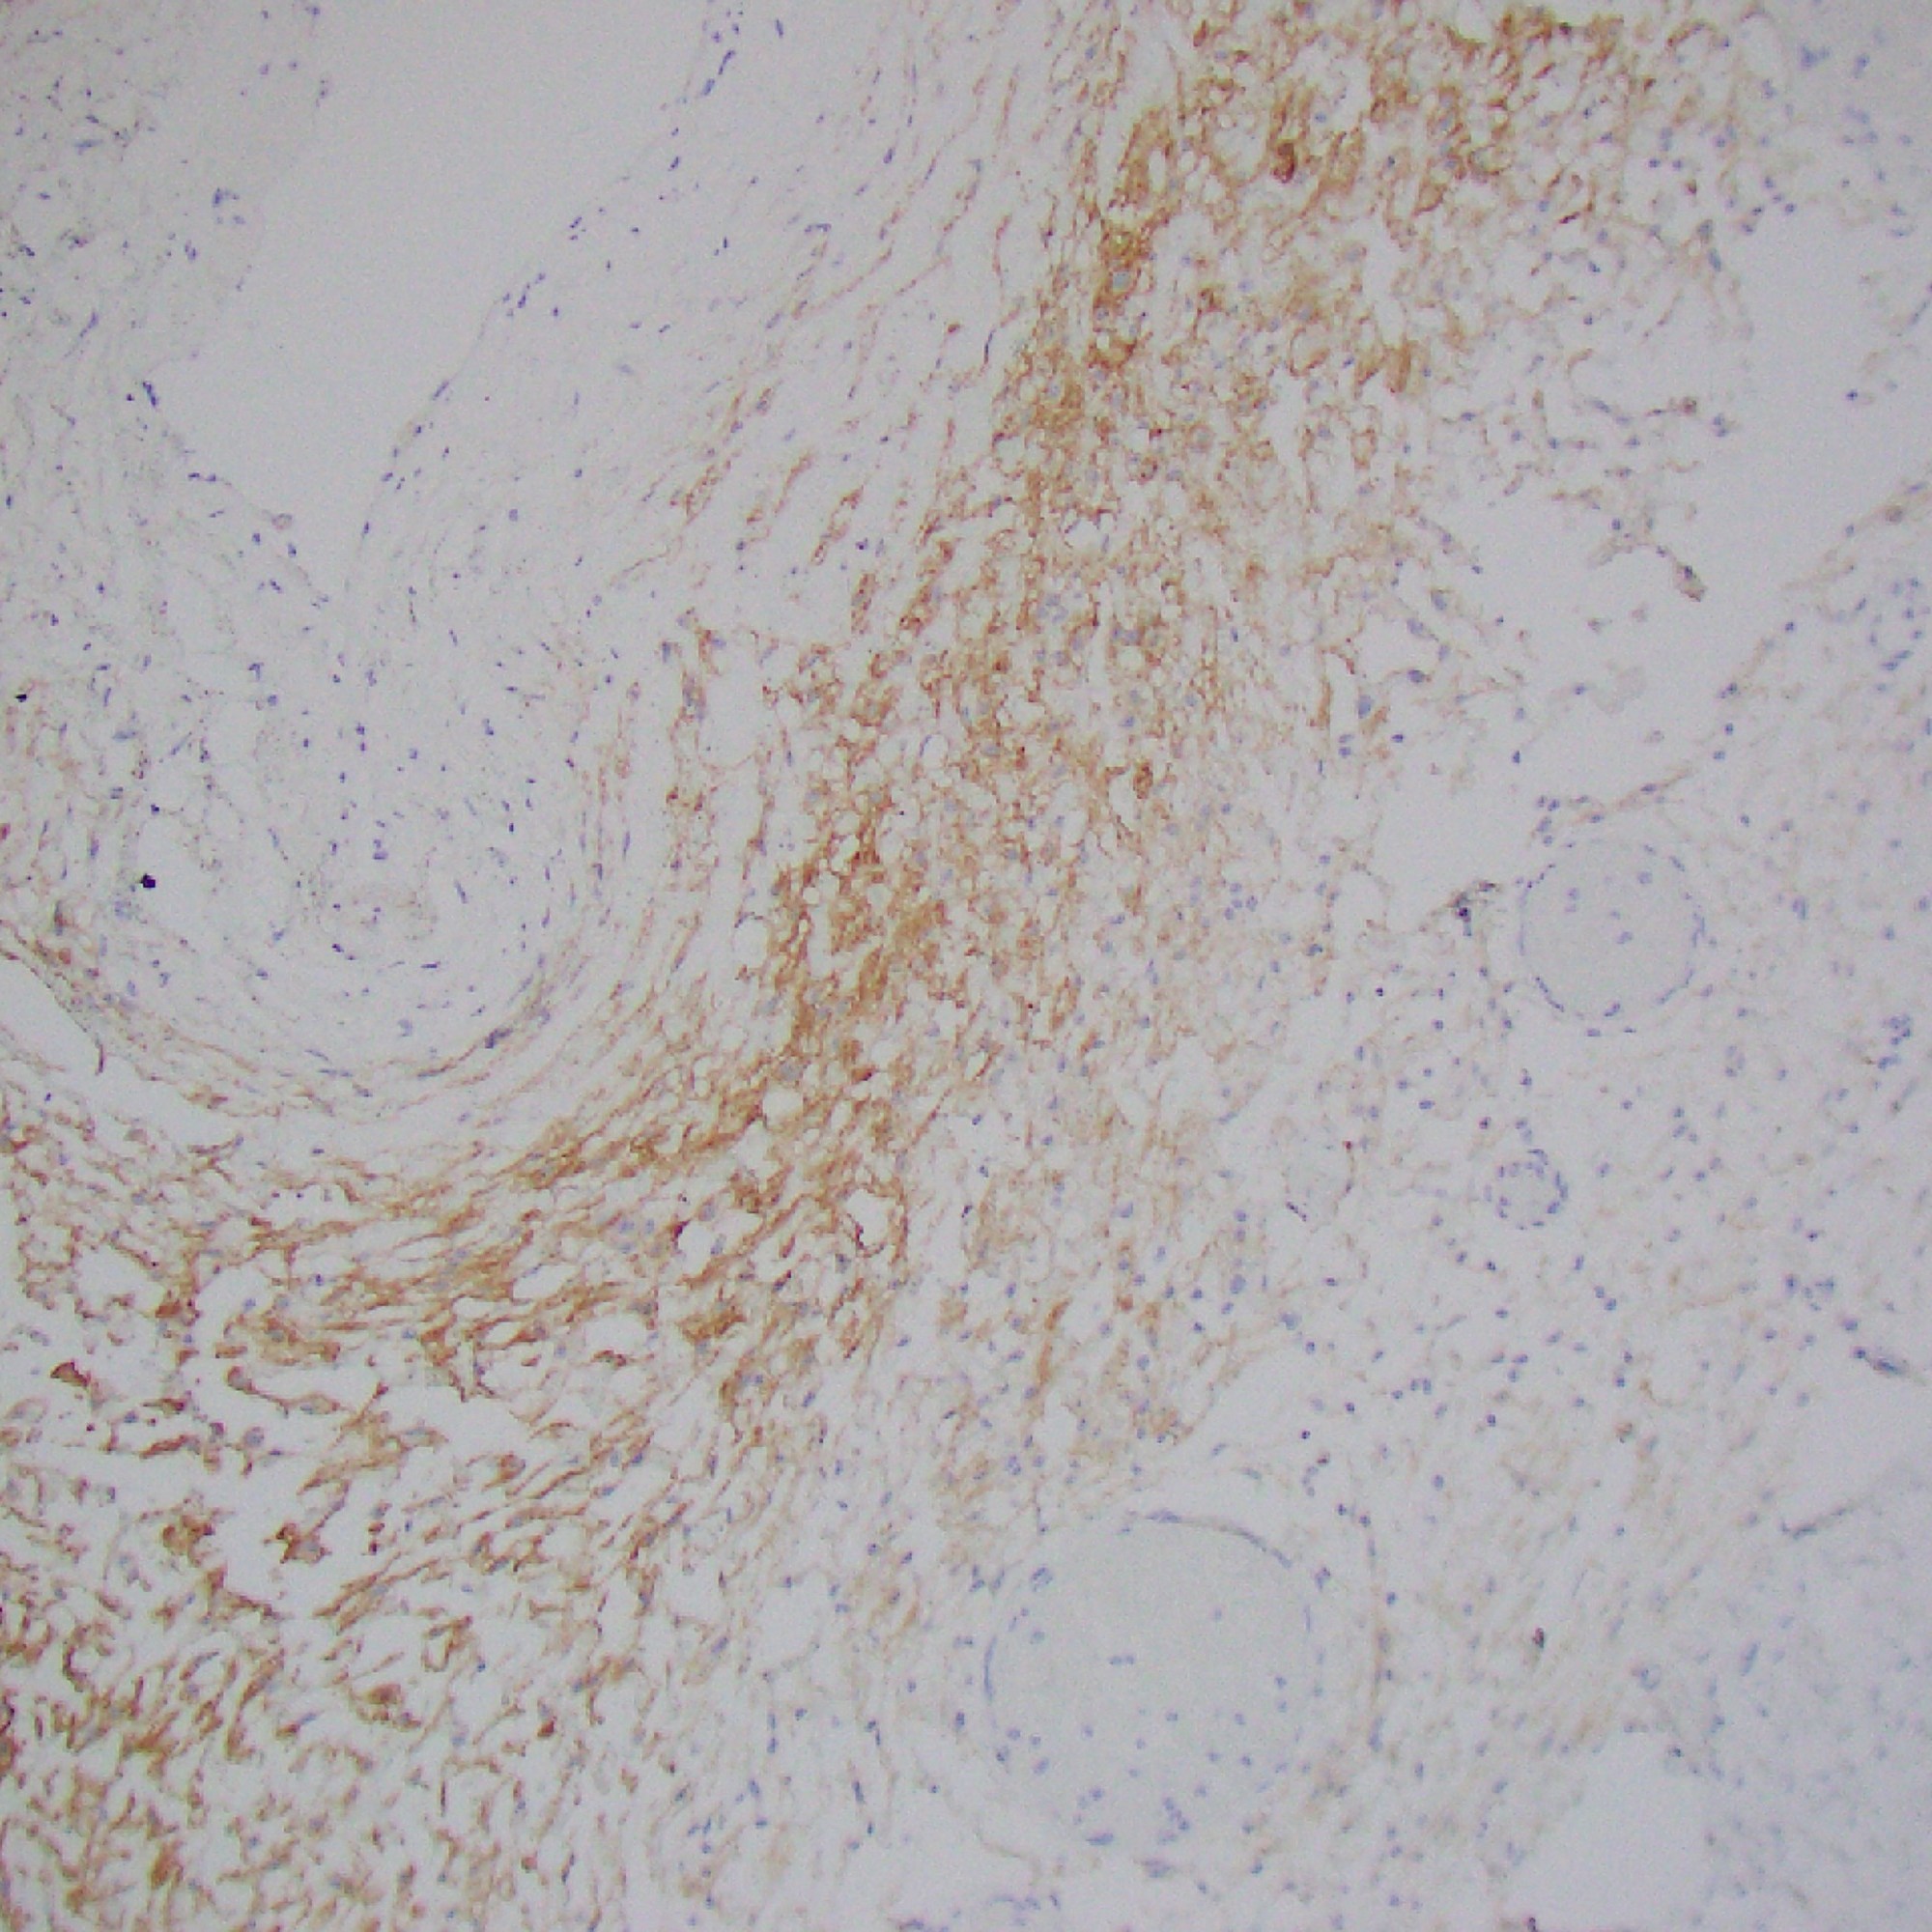

Case 9: Bone lytic lesion

Images

Ill-defined, coalescing nodules of spindled endothelial cells forming elongated slit-like lumina containing erythrocytes and cytoplasmic vacuoles and pericytes. There are occasional platelet-rich microthrombi (left). Dilated crescentic lymphatics surround and intermingle with nodules, most prominently at peripheral margins.

Spindled endothelial cells are positive for CD31, CD34, and ERG, as well as the lymphatic markers, podoplanin, LYVE1, and PROX1

Diagnosis

Kaposiform haemangioendothelioma (KHE)

- A rare, vascular neoplasm usually presenting in children

- GNA14 c.614A>T (p.Gln205Leu) mutation in some cases

- Site:

- Usually in deep soft tissue (extremities, head and neck, trunk, and retroperitoneum; less commonly, the mediastinum, spleen, bone, and testis)

- Can be multifocal, especially in bone

- Tufted angioma (TA): more superficial lesion, otherwise essentially identical to KHE

- Characterized by lobular infiltrates of capillaries and spindled endothelial cells associated with lymphatic vessels.

- KHE and TA cause platelet-trapping syndrome Kasabach–Merritt phenomenon (platelet-trapping syndrome)

- Prognosis:

- Untreated lesions may partially undergo fibrosis and regress – not fully regress

- Often recur

- Large lesions: high mortality due to thrombocytopenia or tumour infiltration

- Medical therapy: first line

- e.g. vincristine, steroids, mTOR inhibitors (sirolimus etc.)

- No distant metastases have been reported.

- Lymph node involvement is rarely seen.

- This may represent multifocal lymphatic chain involvement rather than true metastasis.